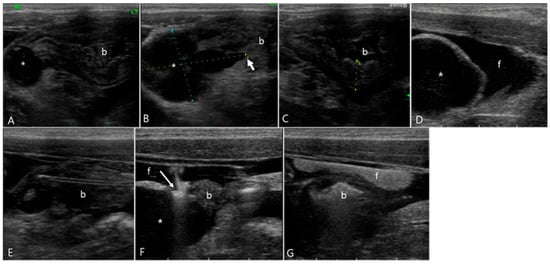

2.1. Case 1